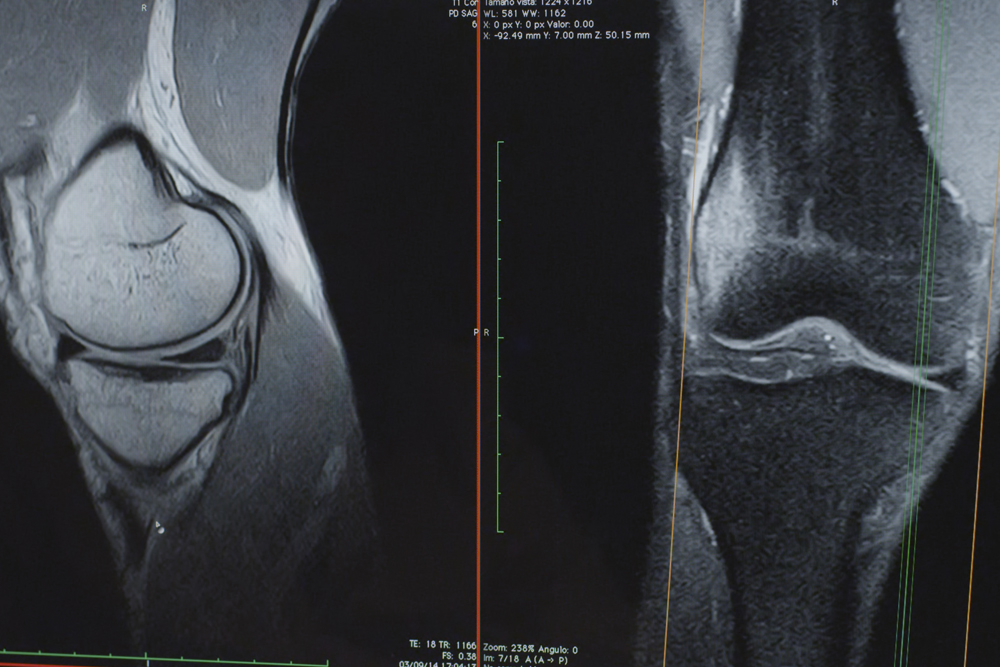

Resonancia Magnética abierta de Alta resolución: 2048 x 2048 pixeles - 256 cortes – 1mm de espesor potencial

Gracias a esta avanzada tecnología de campo magnético permanente, les proporcionamos estudios diagnósticos a 2048 x 2048 píxeles de resolución de imagen, con un alcance potencial de 256 cortes a 1 mm de espesor mínimo. La función de separación de grasa y agua se realiza directamente durante el estudio, al igual que en las resonancias más avanzadas, y el sistema RADAR que posee, corrige los movimientos involuntarios del paciente evitando así errores durante la realización de la prueba. Analizamos el eco de retorno con un avanzado software permitiendo imágenes más nítidas, más estables y de mayor contraste, como la tecnología de predicción y supresión de las corrientes de remolino (ECC system) incorporadas en el propio imán. Con todo ello el potencial de diagnóstico aumenta exponencialmente, permitiéndonos localizar y analizar los artefactos más pequeños que determinada patología pueda originar. Leer más...

Estudios músculo-esqueléticos

Dedos, pie, tobillo, pierna, rodilla, muslo, caderas, sacroiliacas, mano, muñeca, antebrazo, codo, húmero, hombro y escápula.